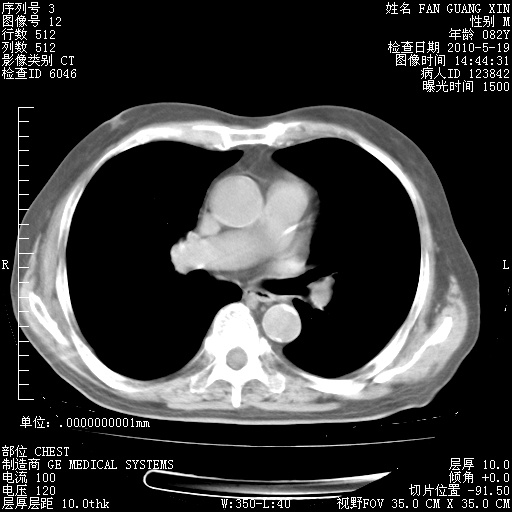

可改为口服强的松40-50mg/d治疗,若病情仍稳定,胸部阴影不再吸收可逐渐减量